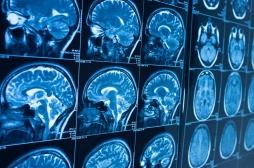

LES MALADIES

SYMPTÔMES